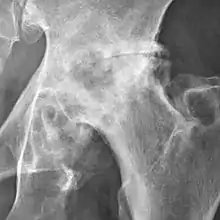

Osteoarthritis of the hip joint may also be graded by Tönnis classification. There is no consensus whether it is more or less reliable than the Kellgren-Lawrence system.[8]

| Grade | Description |

|---|---|

| 0 | No osteoarthritis signs |

| 1 | Mild:

|

| 2 | Moderate:

| 3 | Severe: